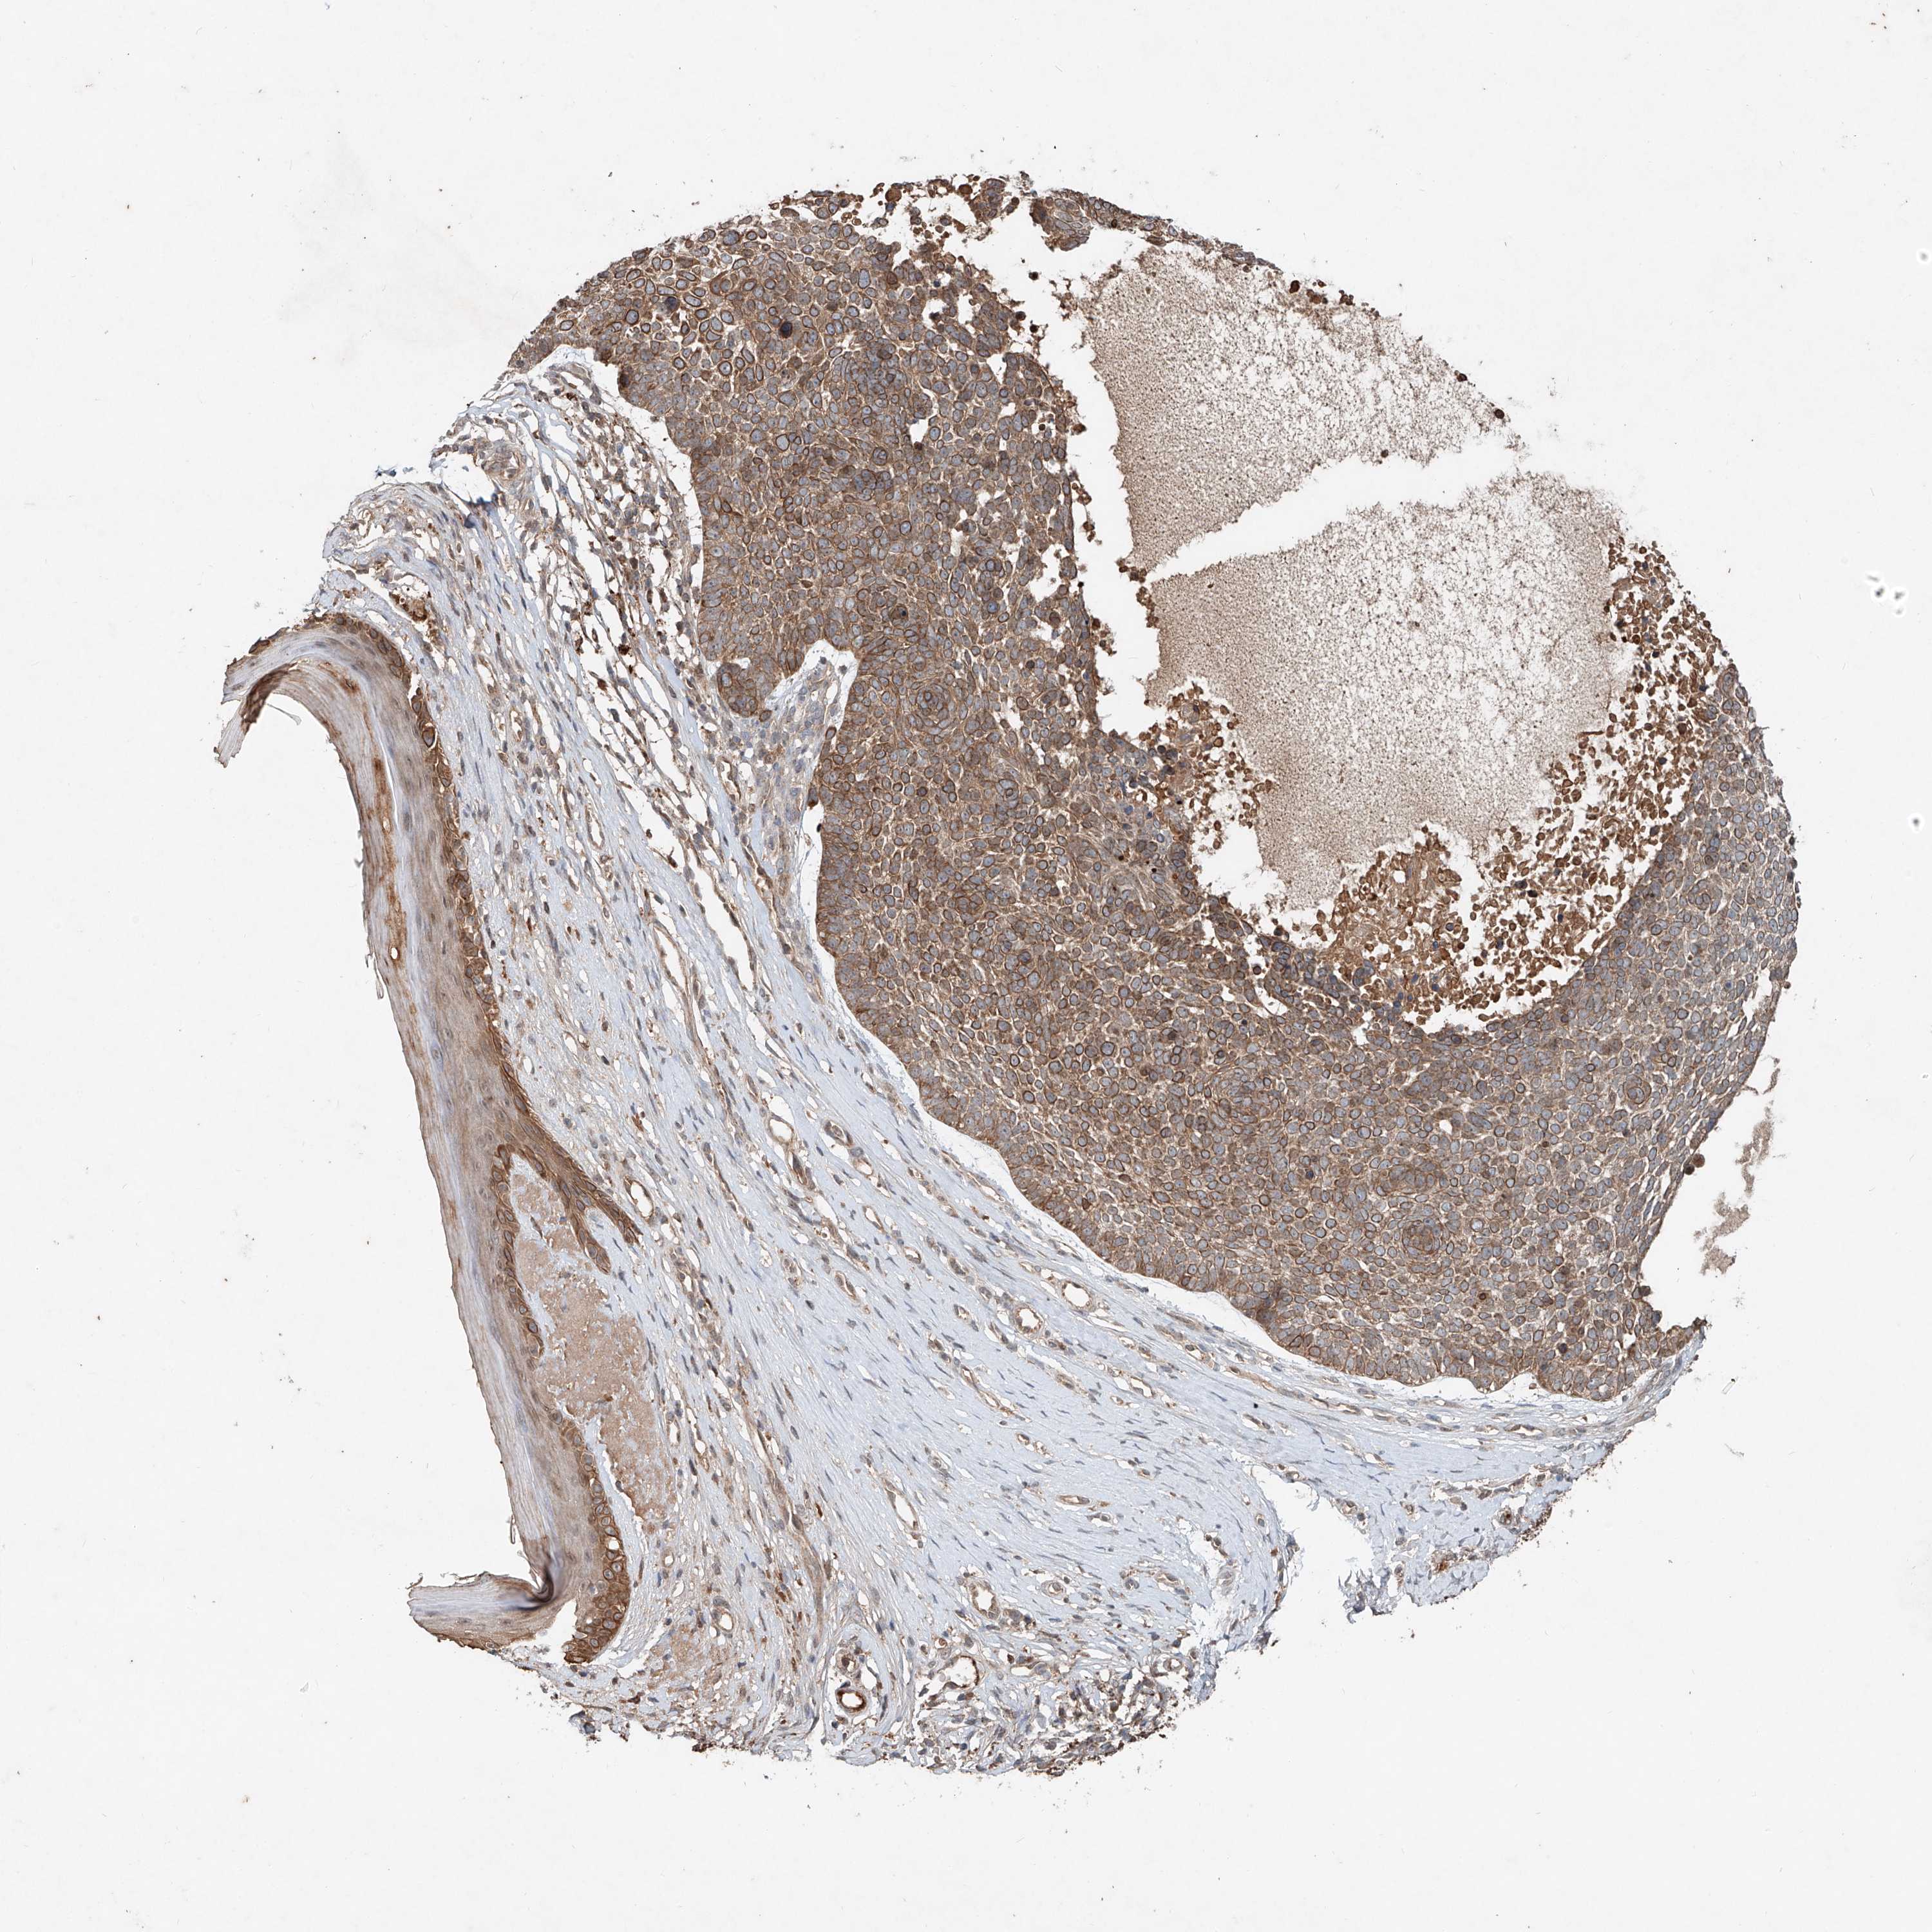

Basal cell and squamous cell cancer

SKIN CANCER - Protein expressioni

A mouse-over function shows sample information and annotation data. Click on an image to view it in a full screen mode. Samples can be filtered based on level of antibody staining by selecting one or several of the following categories: high, medium, low and not detected. The assay and annotation is described here.

Antibody stainingi

Antibody staining in the annotated cell types in the current human tissue is reported as not detected, low, medium, or high, based on conventional immunohistochemistry profiling in selected tissues. This score is based on the combination of the staining intensity and fraction of stained cells.

Each image is clickable and will lead to virtual microscopy that enables deeper exploration of all samples and also displays staining intensity scores, fraction scores and subcellular localization as well as patient and tissue information for each sample.

Antibody HPA029894

Staining

Medium

Intensity

Moderate

Quantity

75%-25%

Location

Cytoplasmic/membranous

Squamous cell carcinoma, NOS